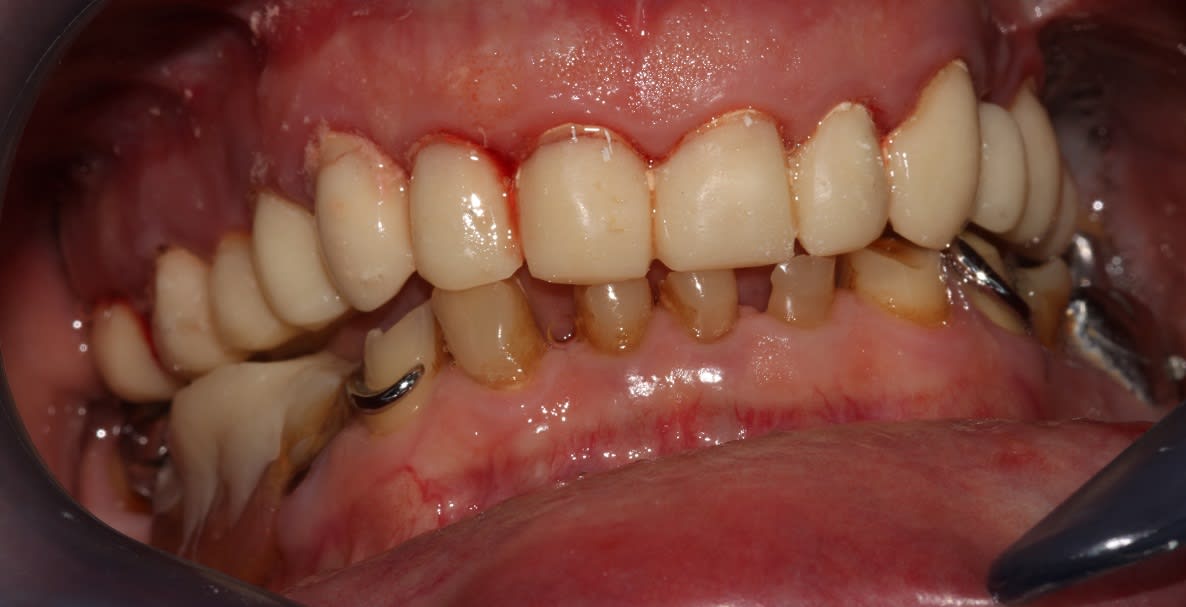

Et putain, une photo en occ serrée, là on voit rien bougre d'âne!

(Au deuxième tour, je relèverai un peu la courbe de Spee sect 1. Au départ je pensais également rentrer un peu 24 25, mais en fait je pense que ça devrait s'équilibrer avec le bas, je vois en fin de semaine. Et le milieu est un peu décentré, mais au bout de 3h j'en avais marre)

Tu pouvais remonter 2mm de plus, facile, non ?

La DV? Si c'est ça je préfère le faire au second tour, ça me laisse plus de laxité, et sur ce genre de cas j'ai tendance à régler le haut comme un complet, donc là on est à la bonne longueur.

je suis pas d'accord sur la longueur des dents maxillaire, mais passons

j'aime pas la forme de 24/25/26, ça me rappelle le dernier cas que j'ai présenté, ou 14/15 faisait verrou)

(pour la morpho secteur 2, les cuspides vest mériteraient effectivement un bon coup de rabot, mais j'attends de voir une fois remontées les antagonistes. Et 36 terminera sur le plateau, la mésiale est bouffée infra osseuse)